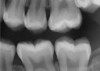

Figure 2 Traditional intraoral bitewing showing limited field of view (Fig 1) compared to the expanded view possible using CBCT (Fig 2).

Figure 2

CBCT can also be used in this same manner to perform an even more common task, bitewing images, which are clinically indicated as often as every 18 to 24 months. For hygiene patients whose films require updating, CBCT offers a “patient-friendly” approach. Given that these films, which are usually performed intraorally, are often taken on an hourly basis in the typical general practice, the technology can be well utilized while also increasing comfort and satisfaction among patients. In addition, due to the expanded field of view that can be achieved with these extraoral CBCT images, they can often be more diagnostically valuable than images produced with an intraoral sensor (Figure 1 and Figure 2).